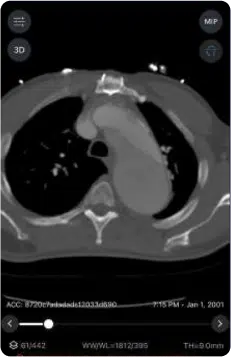

The suite includes specialized modules such as Viz™ Pulmonary Embolism, which offers AI-powered clot detection and automated RV/LV ratio calculation. This module securely detects and triages central and segmental embolisms, expediting treatment decisions and facilitating communication through a built-in chat. Another key module, Viz Aortic Disease, provides AI-powered detection of suspected abdominal aortic aneurysm (AAA) and aortic dissection. Viz.ai emphasizes unparalleled accuracy and performance, with published post-market validation demonstrating high sensitivity and specificity for PE, Aortic, and AAA detection. By improving diagnostic acumen and expediting critical decision-making, Viz Vascular aims to save lives and improve patient outcomes.

- Pulmonary Embolism (PE) Module: Offers AI-driven clot detection, automated RV/LV ratio calculation, and secure triage of central & segmental embolisms to expedite treatment decisions.

- Validated Accuracy & Performance: Demonstrates high sensitivity and specificity (e.g., PE 91%/92%, Aortic 96%/98%, AAA 96%/95%) with real-world post-market validation.